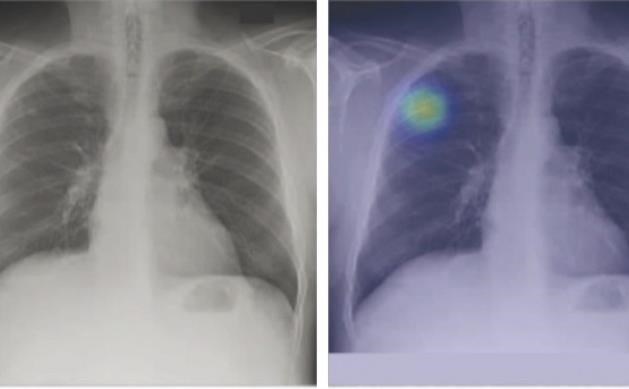

سرطان ریه نوعی بیماری بدخیم است که در سلولهای ریه ایجاد میشود. تشخیص آن معمولاً با سیتیاسکن، PET Scan، نمونهبرداری (بیوپسی) و آزمایشهای تکمیلی انجام میشود. تشخیص زودهنگام نقش مهمی در افزایش شانس درمان دارد.

شبیهسازی اولین جلسه پرتودرمانی است که در آن درمان انجام نمیشود. در این مرحله با کمک تصویربرداری، موقعیت دقیق تومور مشخص و برنامه درمانی طراحی میشود.